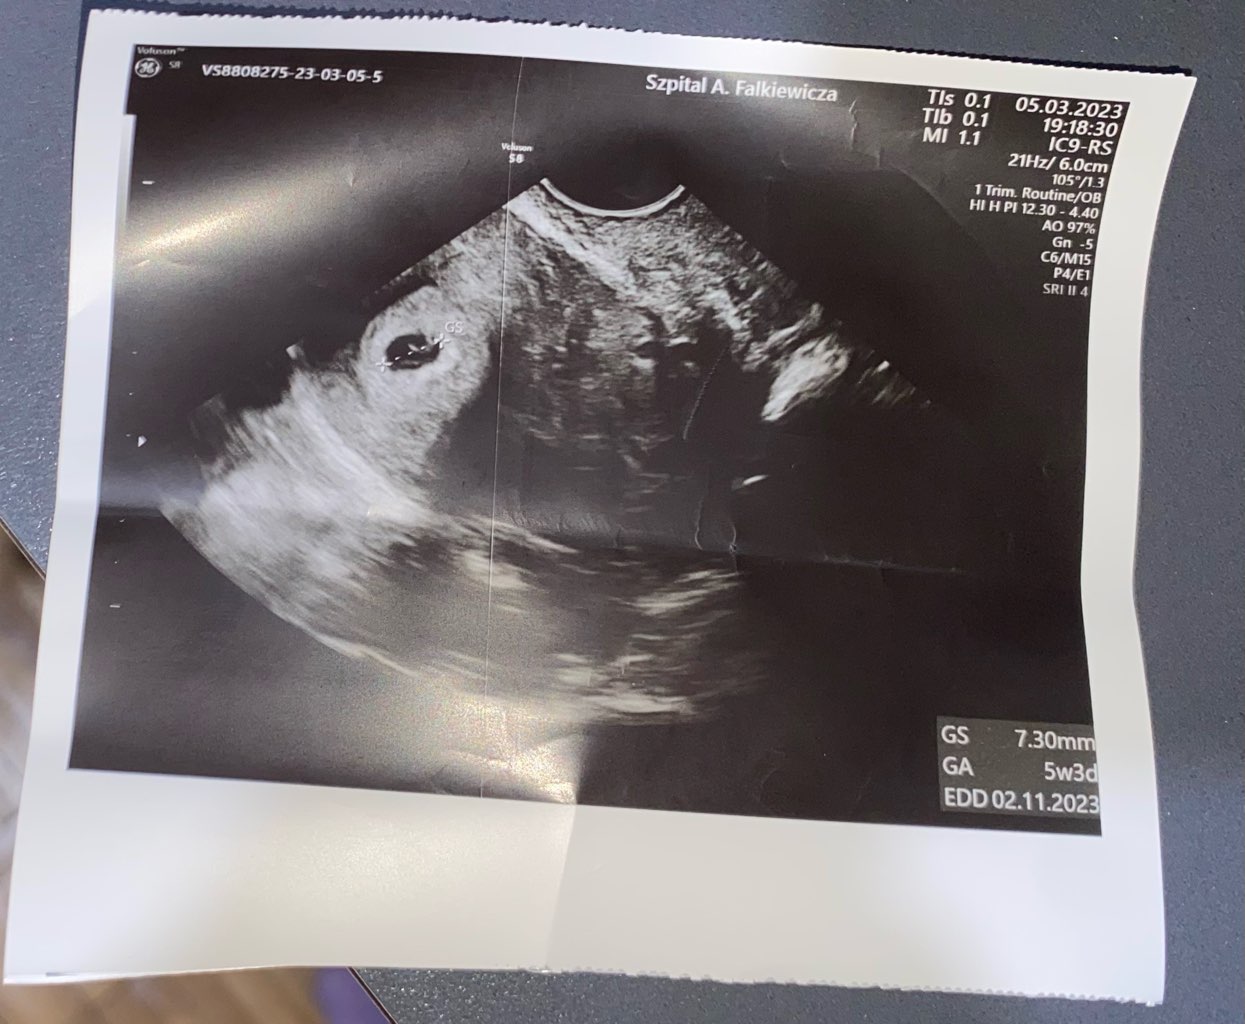

Dziewczyny, które były na USG w 5+0 lub coś koło tego - co było widać na USG? Był już pęcherzyk?

ja miałam badanie w 5+3, był pęcherzyk. Zostawiam zdjęcie jak to wyglądało